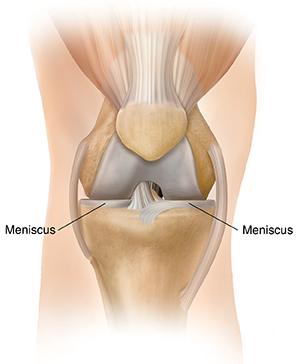

Having Meniscal Transplant Surgery

Meniscal transplant surgery is a surgery to replace missing or damaged meniscus (cartilage) in the knee. The meniscus is replaced with one from a cadaver donor.